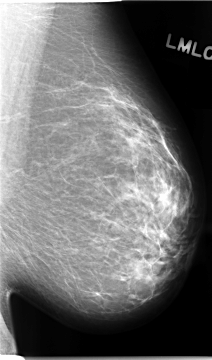

C_0094_1.LEFT_MLO

ics_version 1.0

filename C-0094-1

DATE_OF_STUDY 5 8 1994

PATIENT_AGE 40

FILM_TYPE REGULAR

DENSITY 2

DATE_DIGITIZED 19 11 1997

DIGITIZER LUMISYS LASER

LEFT_CC LINES 4720 PIXELS_PER_LINE 2744 BITS_PER_PIXEL 12 RESOLUTION 50 NON_OVERLAY